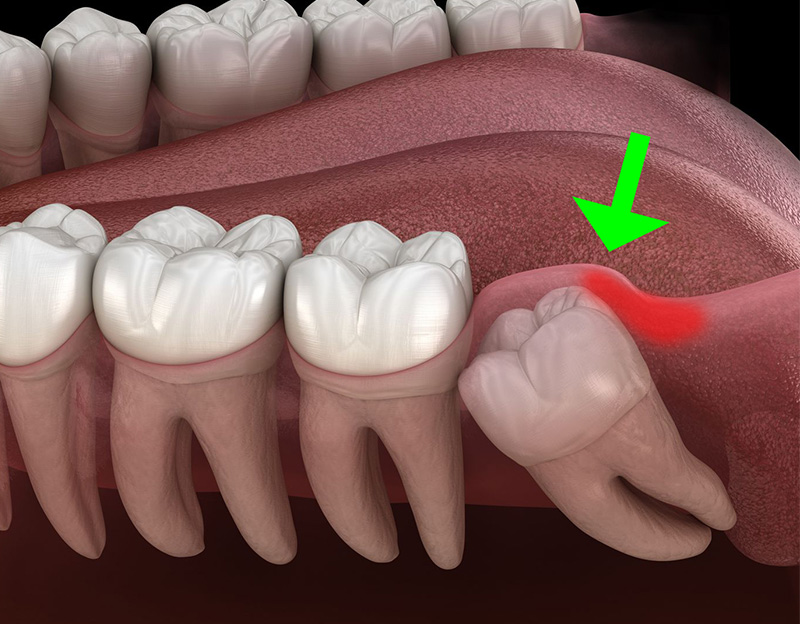

智齿是第三磨牙,长在牙槽尽头。进化论者认为,人类和猿猴的祖先下颚和牙齿比我们大。在进化过程中,颌骨变得越来越小,智齿空间越来越少,因此引起了许多问题,残留至今的智齿很多时候只能拔除处理。按进化论者的说法,智齿问题简而言之就是脑部变大,牺牲了颌骨的大小造成的。1,2

事实真的如此吗?对复杂的下颌关系深入研究会发现,当今大多数智齿问题是因为食物结构发生了变化,从粗磨食物变成精细化加工的食物,从而导致下颌关系紊乱。

研究表明,现代社会中智齿所遇到的问题并不是由于环境造成的变异,而是饮食结构改变造成的问题,现代化社会中人们吃的大多是经过精细加工的食品,质地柔软,缺少磨料,牙齿得不到应有的锻炼,也不易保证健康的咬合关系。

西方社会曾有一波预防性拔智齿的趋势,跟曾经流行的阑尾切除类似,这是抱着智齿是退化器官的观念导致的错误医疗实践,可能多达数十亿颗牙齿的拔除是没有必要的。拔出智齿可能会导致术后疼痛,肿胀和颞下颌关节功能障碍。7 拔牙还可能损害牙龈并引起骨质流失,从而对第二颗磨牙产生不利影响。8